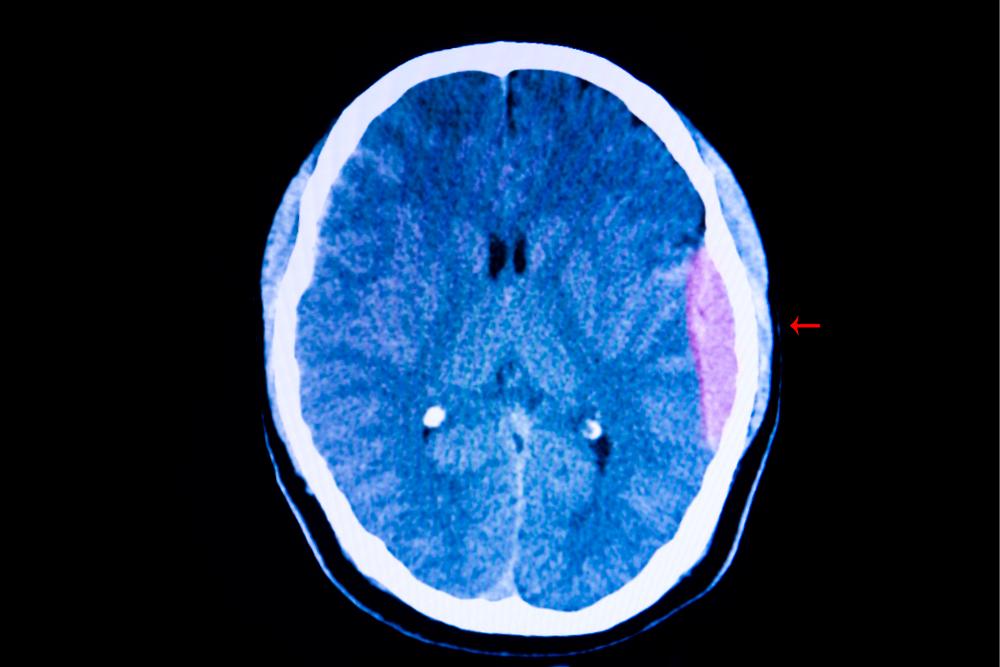

Dependiendo de la zona afectada, los hematomas pueden clasificarse en tres grandes grupos. Por un lado, tenemos los más comunes, los subcutáneos, es decir, los que se producen justo debajo de la epidermis y aquellos que puedes ver fácilmente. Esos son los famosos moretones. Pero también podrías tener uno intramuscular o perióstico, es decir, que el contenido de los vasos termina dentro de los músculos y de los huesos, respectivamente. Este último es el más doloroso y suele estar acompañado de otras complicaciones como daño en los ligamentos, aunque es más leve que una fractura o quebradura.

Verás que la mancha que en algún momento fue más bien rosácea puede ir oscureciéndose hasta llegar al azul y pasar al amarillo-verdoso para luego alcanzar el color original de la piel. Por supuesto, los hematomas vienen acompañados de dolor en la zona exacta y las cercanías y muchas veces de la inflamación de los tejidos (es decir, un chichón). Eso sí: es importante que le prestes atención al dolor; si es muy fuerte y además sientes presión en la herida, debes consultarlo en un centro médico, especialmente si no sabes con certeza el origen del moretón porque dudas de haberte golpeado. En estos casos, podría ser un síntoma de hemorragia interna.